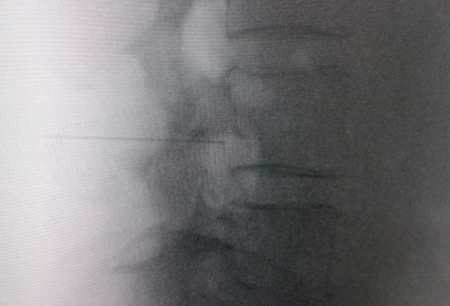

Access by transforaminal route is the most widely used (4). The patient is placed in prone position with an abdominal pillow to reverse physiological lordosis. The most commonly used RF needles or cannulas are 20 or 22 G diameter and 98 mm long with 0.5 or 1 cm active tip. Following asepsis with alcoholic chlorhexidine and placement of sterile fields, radiological approaches in anteroposterior, oblique and lateral incidence are performed. In anteroposterior incidence and moving the arc in cranio-caudal direction, the double arc of the lower vertebral edge is deleted. In oblique incidence between 20 and 30 degrees ipsilateral to the DRG to be treated, the classic image described as “Scotty Dog” will be displayed, which is the result of bringing the articular facets and the spinous process closer to the contralateral side. The entry point will then be immediately below the pedicle. After local anesthesia with 1 % lidocaine, the needle will be inserted following a tunnel vision and will not advance beyond half of the pedicle in this projection to prevent neural injury. In lateral projection, it will be inserted into the roof of the neuroforamen (Figures 1 and 2) but the final location will be determined by sensory-motor nerve stimulation. Sensory stimulation is to cause paresthesia or pain in the affected territory with stimulation between 0.3-0.6 v. During motor stimulation fasciculations can be caused in the affected territory with a voltage of twice that necessary to cause paresthesia. If an intraganglionar denervation, promulgated by some authors, is desired, both sensory and motor stimulation will be positive at less than 0.3 v. As this is a more painful procedure, it is advised to administer local anesthetics after the painful stimulus and before treatment. The impedance should be kept below 450 ohms, which is achieved by infusing saline before proceeding with RF (4). The use of contrast is good practice, as it rules out the intravascular and intrathecal position of the radiofrequency cannula.

Fig. 2. Anteroposterior radiological view of a radiofrequency cannula placed in neuroforamen L4-L5, in the so-called safety triangle, after contrast injection. A thickening of the radiculogram is observed at the roof of the neuroforamen, which may correspond to the dorsal root ganglion of L4